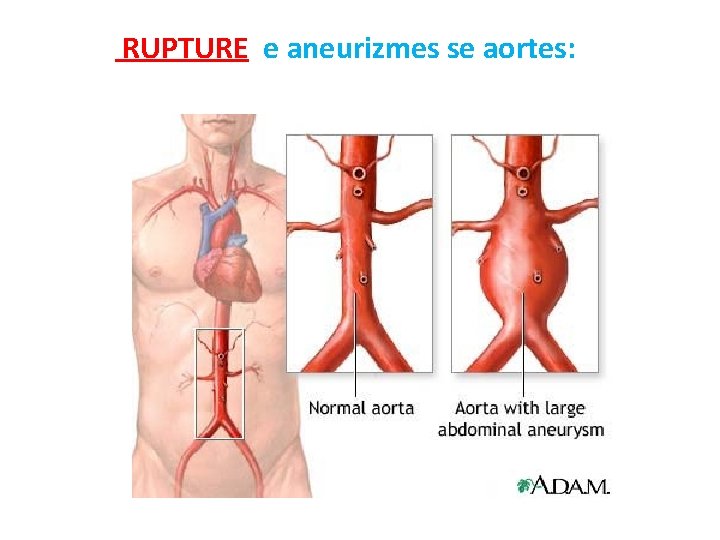

RUPTURE e aneurizmes se aortes: